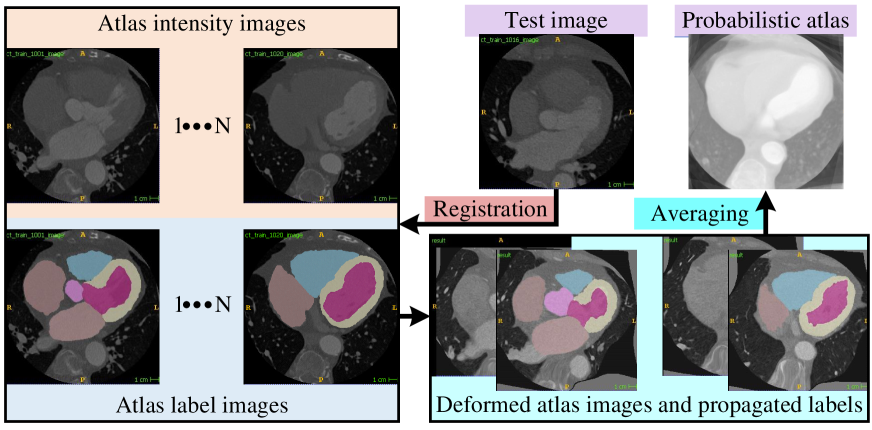

Fig. 2 demonstrates the proposed pipeline for atlas-based WHS, where the registration is the crucial integral step to deform a moving CT or MRI image to align with a fixed CT or MRI image spatially.

Let us consider that is an unseen fixed cardiac image (CT or MRI) to be segmented (). is a set of moving images to build atlases, where , , and are the intensity image, its corresponding label image, and the number of member images in the reference volumes, respectively. We perform moving-to-fixed registration (non-rigid) to construct a deformed set, , where and are the resultant deformed intensity image and its corresponding deformed label image. The deformed intensity image () and its corresponding deformed label image () are averaged to construct probabilistic atlas () and probabilistic label (), respectively, using (1) and (2), respectively.

| (1) | |||

| (2) | |||

where is a transformation between pair of and . For voxels and target substructure regions, both the and probabilistic atlas is a matrix with elements, and each element () represents the anatomical knowledge about the heart provided by training samples on the prior probability of voxel belonging to a particular tissue class .

The intensity image () is appointed as the moving image for deforming to the unseen fixed images () using a non-rigid transformation () [39, 40, 41]. The algorithm of is a combination of a global and local transformations as . The global () is an affine transformation allowing scaling, translation, rotation, and shearing of , whereas the local () is a free-form deformation model based on B-splines [42]. However, in our pipeline, we formulate the registration as an optimization problem in (3) for maximizing the similarity between and employing the .

| (3) |

where is an optimal transformation to spatially align to . is a cost function, which we minimize by designing a pipeline combining different algorithms. The cost function () is optimized using adaptive stochastic gradient descent optimizer [43]. Other crucial algorithms in our proposed pipeline, such as interpolator, metric, and resample-interpolator, are the B-Spline algorithm with an order of , mutual information [44] with histogram bins of , and B-Spline algorithm with an order of , respectively. A multi-resolution strategy, with resolutions of , is used to bypass local minima [45]. We use Elastix-111https://elastix.lumc.nl/doxygen/index.html [46] to implement our proposed registration pipeline. In this work, a full probabilistic atlas is built and evaluated following a leave-one-out evaluation strategy [37].

This subsection presents and designs several integral strategies in our proposed pipeline (see in Fig. 2) to delineate different anatomical substructures (see in Table I); once the moving images are deformed to a fixed image employing a non-rigid registration.